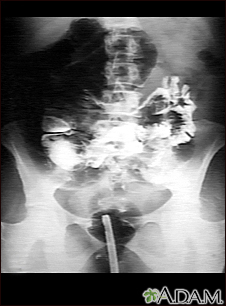

Volvulus - x-ray